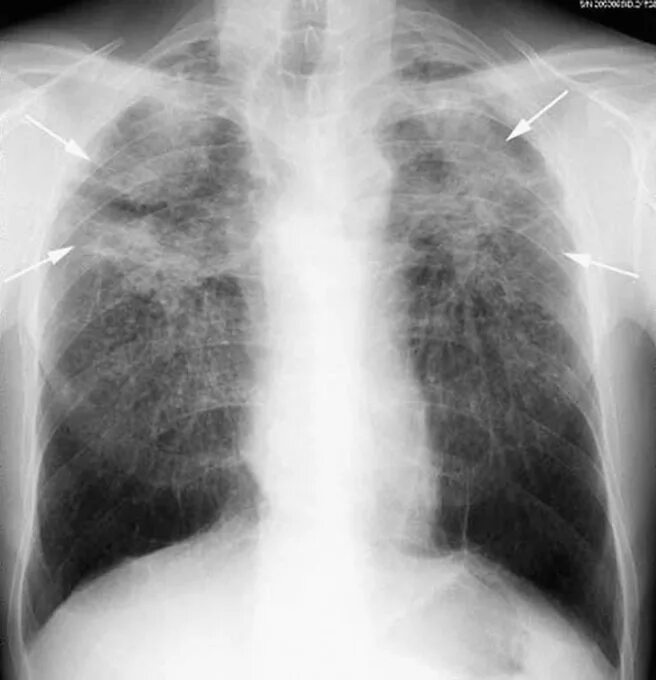

Пневмосклероз рентгенограмма